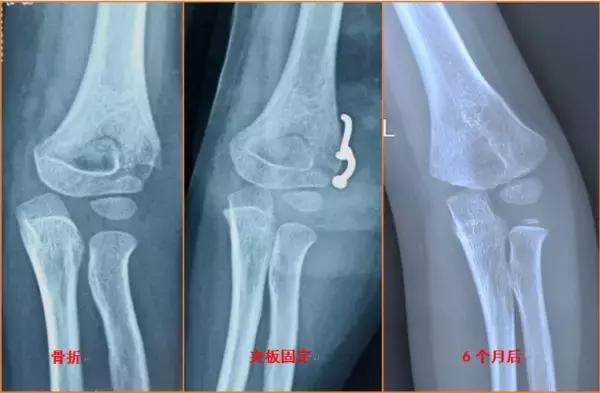

就目前流行病学研究,先天性肘内翻畸形非常罕见,80%的肘内翻都是儿童时期肱骨髁上骨折治疗不当导致,肱骨髁上骨折的远端向内侧倾斜,内侧骨质压缩嵌插,骨折外侧端张开及骨折扭转未得到有效纠正,骨折畸形愈合后导致肘内翻畸形。其他还有肱骨内髁骨折处理不当等因素导致。

肘内翻畸形如何纠正呢?这个时候我们需要拍摄健侧上肢的提携角,患侧肘内翻角度加上对侧上肢提携角就是我们需要矫正的角度,通过去掉一个外侧的三角形骨块就可以达到我们需要的力线和外观啦。当然更大角度的肘内翻需要不同的截骨方式或者配合尺神经松解术。